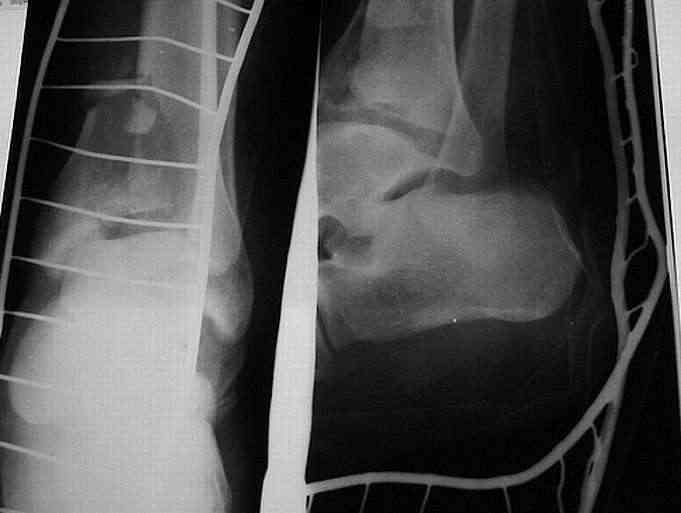

Мной был демонтирован АВФ, удалены все спицы. Больной некоторое время лечился консервативно (шина Белера, антибиотики, перевязки). По заживлению и купировании гнойно-воспалительного процесса была произведена осткрытая репозиция, накостный остеосинтез 1/3 трубчатой пластиной.Такой вариант был принят из-за жуткого остеопороза и отказом больного от предложенного артродезирования голеностопного сустава сразу. Послеоперационный период без особенностей. Через год, больной пришел на осмотр на своих двоих, без дополнительной опоры, с жалобами на боли приходьбе в обл. г/стопа и с желанием замкнуть сустав. В операционной столкнулся с неожиданной проблемой по удалению пластины, она была глубоко вмурована в толщу склерозированного метафиза на глубину 1.5 см; удалить не рискнул (считал, что металл помешает в ходе реконструкции и требуется его удаление).

Было решено, уже по ходу операции, выполнить артродез болтом-стяжкой, тем самым компрессируя резецированные суставные поверхности и смещая стопу латерально, дабы нивелировать варусную деформацию и восстанавливая тем самым опорную ось всей конечности.

ЗЫ: Прошу прощения за очень низкое качество представленных ренгенограмм. Буду очень признателен за комментарии.